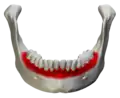

The alveolar ridge refers to one of the two thickened bony crests, that exists in the upper and lower portions of the jawbone and house the sockets of the teeth.[28] As the rate of tooth loss in the population increases either due to early extraction, trauma, or other systemic diseases, the use of implant therapy has increased as a form of tooth replacement therapy.[28][33] Dental implants are a way to replace missing teeth, as they consist of a titanium surgical component that is placed in the alveolar ridge of the jawbone.[34] The implant then acts as a prosthetic device that can hold either a crown, bridge, or denture on its external surface.[34] For the implant placement to be successful, there needs to be enough alveolar bone to support and stabilize the dental implant.[34] It has been determined that many factors can contribute to the loss of both the vertical and horizontal height of the alveolar bone.[35] These factors can include resorption of the bone after tooth removal (affecting the quality and quantity of the bone), the presence of periodontal disease, the age and gender of the patient, smoking habits, the presence of other systemic diseases, and oral hygiene habits.[36] Although dental implants tend to have a high success rate, of about 99%,[37] studies show that if an implant were to fail, it occurs more often in the front portion of the upper jaw.[38] More research is required to determine why this occurs, but it has been theorized that the alveolar bone in the upper jaw has a thinner cortical plate and lower bone density than that of the lower jaw.[38] As bone loss in the alveolar ridge becomes an increasing problem for the success of dental implants, research has been focused on the development of new surgical techniques and biomaterials that can be used to either maintain current bone levels, or to stimulate the growth of new alveolar bone through osteogenesis.[39][40][41]